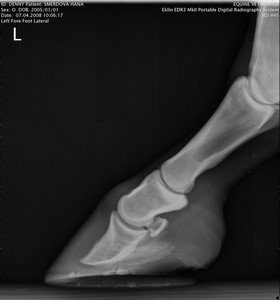

RTG Levá přední (07.04.2008)